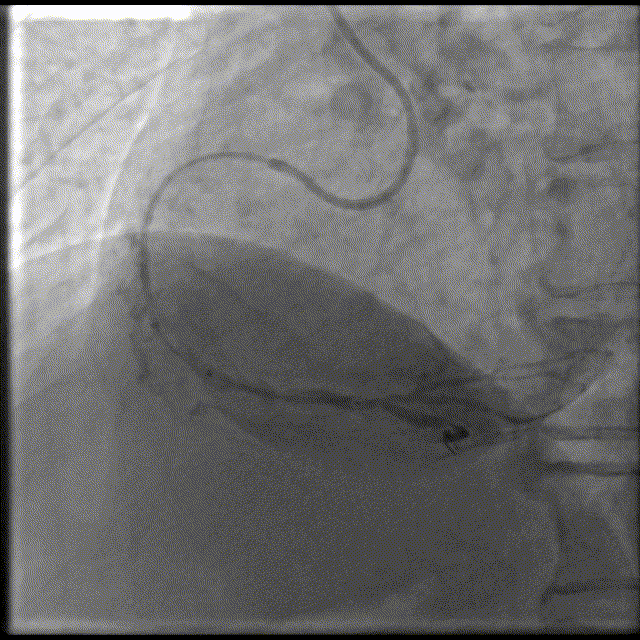

6F JR4.0GC

GW:Runthrough

球囊:2.0x15mm,8-12atm

球囊扩张不充分,可见夹层,加压再扩张。

头位造影:RCA近中段钙化迂曲,第二转折处中度狭窄。

2.75x28mm支架,不能通过近中段。